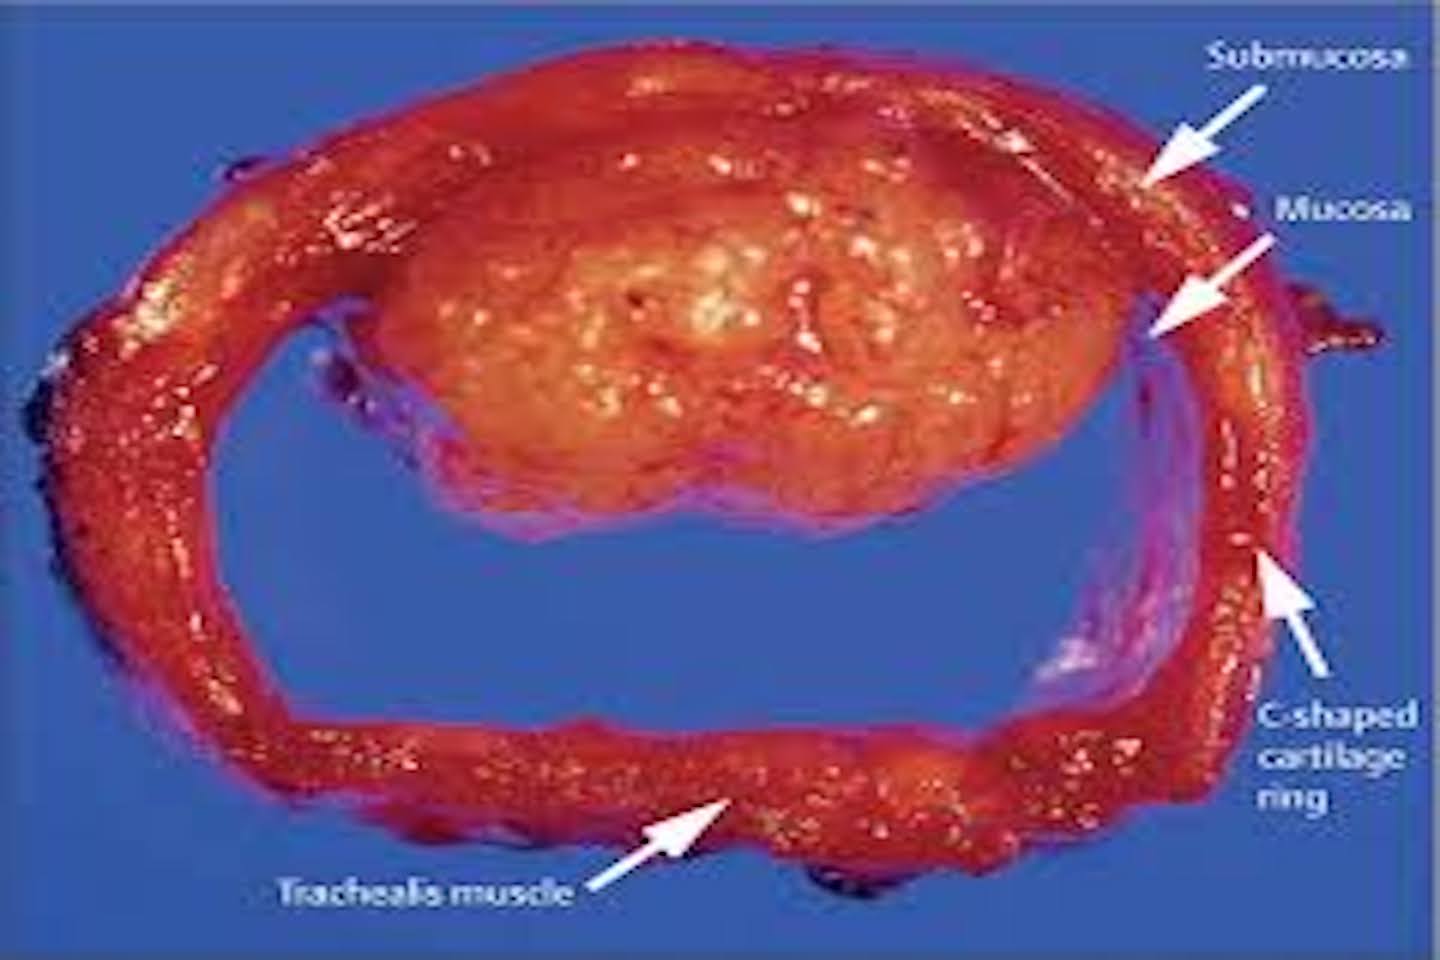

When she presented at the OPD, the patient had severe breathing difficulty along with stridor and was immediately admitted for urgent care. CT chest scans confirmed the presence of a tracheal tumor. To relieve the airway obstruction, a bronchoscopy-guided debulking procedure was performed, which provided temporary relief in breathing. Histopathology later revealed that the tumor was a poorly differentiated primary tracheal malignancy.

Dr. Utkarsh R. Ajgaonkar, Consultant Surgical Oncologist, said, Patient presented in my OPD with progressively worsening breathing (stridor) and was immediately admitted and kept on oxygen support.’ Primary tracheal tumors are exceptionally rare, and performing a thoracoscopic-assisted resection requires meticulous planning. Primary tracheal malignancies are extremely rare, accounting for <0.1% of all cancers, with an incidence of 2–3 cases per million per year. Causes of this cancer can be smoking, air pollution, occupational exposure to toxins, chronic inflammatory conditions like tracheitis, genetic, or idiopathic in many patients. If not diagnosed and treated early, these patients can end up with progressive breathing difficulty and asphyxiation, recurrent lower respiratory tract infections, bleeding from the tumor, local invasion in surrounding organs and vessels, and metastasis to distant organs. The goal was to remove the tumor completely while minimizing surgical trauma and preserving airway function.

Dr. Utkarsh R. Ajgaonkar further added, “The patient underwent a thoracoscopic-assisted tracheal resection along with paratracheal lymph node dissection, i.e., removal of the affected segment of the trachea and joining of the two ends with removal of draining lymph nodes. This was a very challenging case because we had to remove nearly 4 to 4.5 cm of the affected part of the trachea. After removing the diseased segment, we carefully joined the upper and lower ends of the trachea immediately to restore the airway. At the same time, we also removed the nearby paratracheal lymph nodes to ensure complete clearance of the disease. The technically demanding procedure was performed using minimally invasive techniques, ensuring precise tumor removal while reducing postoperative pain and complications. Anaesthetic management was critical for a safe surgery, and the patient was extubated on the first postoperative day. The uneventful procedure lasted for approximately 5–5.5 hours. Follow-up bronchoscopy on day six confirmed a healthy airway anastomosis, and the patient was discharged on day eight with stable recovery. As a precaution, the patient was advised to avoid neck movements for three weeks post-operatively.”